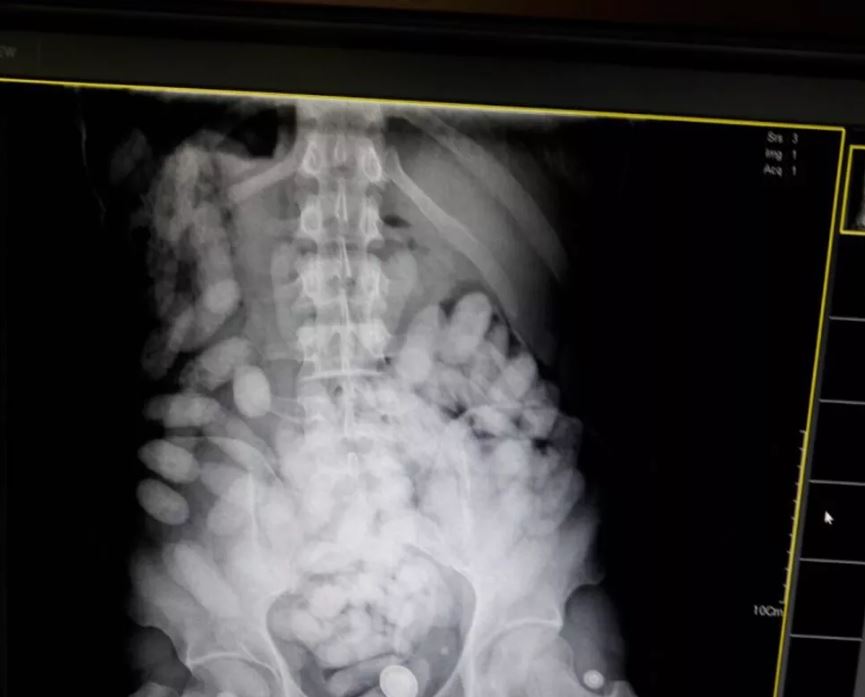

De acordo com a PC, as drogas eram colocadas dentro do corpo dos envolvidos para burlar as fiscalizações dos aeroportos.